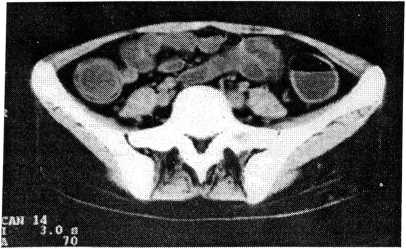

При болезни Крона у больных отмечалось значительное (до 1,5 см) утолщение стенки кишечника, но при этом оно было однородным, без двойного контура. Утолщение стенки кишечника, в отличие от такового при инфильтративном раке, носило эксцентричный, сегментарный характер. Просвет кишечника в пределах пораженного сегмента имел суженный извитый зигзагообразный ход. При сканировании он напоминал свинцовую трубку, что было связано с глубокими продольными трещинами в стенке кишечника (рис. 2).

Рис. 2. Томограмма при болезни Крона. Патологический процесс располагается в нисходящем отделе толстой кишки. Просвет кишечника сужен (“свинцовая трубка”). Стенка кишечника значительно утолщена.

При болезни Крона с помощью РКТВК у 2 больных были выявлены дивертикулоподобные выпячивания стенки кишечника. В результате все эти признаки позволили у 2 больных исключить язвенный колит и установить болезнь Крона. Значительным преимуществом РКТВК по сравнению с ирригографией была возможность определения состояния других органов брюшной полости. Так, у 2 больных была установлена желчнокаменная болезнь, у 2 — мочекаменная, у одной — нефроптоз, у одного — метастазы опухоли в печени. При наших исследованиях осложнений при проведении РКТВК ни у одного больного не возникло.